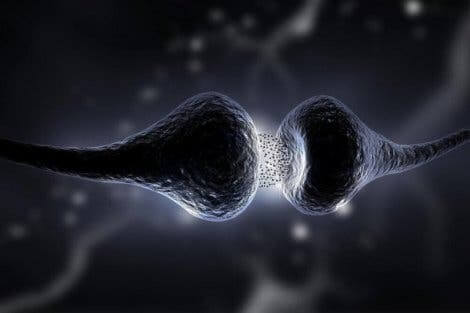

시냅스는 뉴런이 서로 통신하는 부위이다. 우리가 태어날 때는 대뇌 피질에 한 뉴런당 시냅스의 수가 제한되어 있다. 실제로 전문가들은 약 2,500개의 시냅스가 있다고 생각한다. 하지만 시간이 지나면서 이 숫자는 한 뉴런당 거의 10,000개의 시냅스로 높아진다.

바로 우리가 성장하면서 다양한 행동을 경험하고 배우기 때문이다. 이 모든 것이 새로운 뇌 연결을 형성하고 다른 연결을 강화시킨다. 하지만 사용하지 않는 시냅스는 죽는다는 것을 의미하기도 한다.

뇌의 신경가소성으로 인해, 새로운 시냅스는 평생 동안 형성되거나 재생될 수 있다. 실제로 이는 다양한 분자와 화학 메커니즘을 통해 나타난다. 따라서 새로운 것을 배울 때마다, 시냅스가 강화되거나 심지어 더 많아지기도 한다.

- 뉴런의 흥분성이 회복된다. 이는 뉴런의 내부와 외부 간 이온의 균형이 복구되기 때문이다.

- 특히 축삭 돌기를 포함한 손상된 뉴런의 일부가 재생된다.

- 활성화되지 않은 회로가 회복한다.

이러한 반응은 매우 복잡하다. 하지만 그 결과, 뇌에 더 많은 연결이 생긴다.